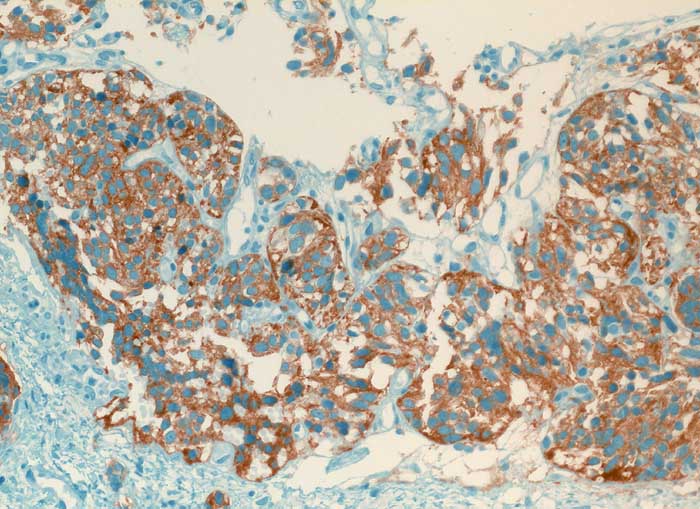

PathoPic ID 6339 - Karzinoid

Karzinoid

benigner Tumor

Lunge

Lunge, Mediastinum mit Thymus

Die spindeligen Tumorzellen exprimieren den endokrinen Marker Synaptophysin.

V. a. Tumor pulmonal

Histologie

Immunhistochemie

Synaptophysin

200

58

männlich